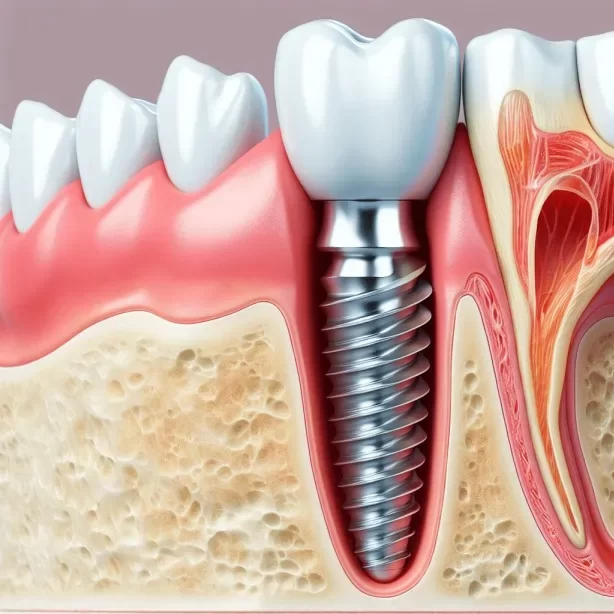

Más información Agendar por WhatsAppReemplazo fijo

Reemplazo de piezas dentales con implantes de titanio para recuperar función y estética.